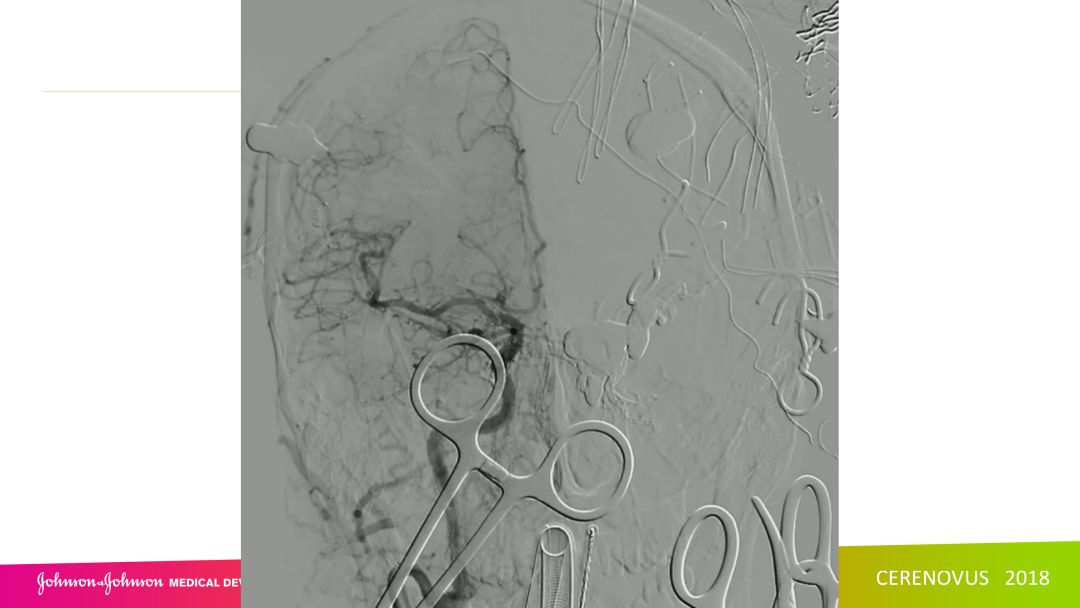

复合手术治疗海绵窦区硬脑膜动静脉瘘一例